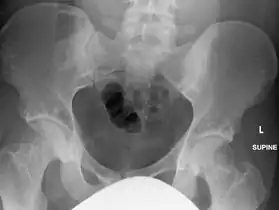

In terms of the diagnosis Osteopoikilosis is radiographically evaluated via the presence of multiple symmetrical circular sclerotic opacities [2]

The radiographic appearance of osteopoikilosis on an X-ray is characterized by a pattern of numerous white densities of similar size spread throughout all the bones. This is a systemic condition. It must be differentiated from blastic metastasis, which can also present radiographically as white densities interspersed throughout bone. Blastic metastasis tends to present with larger and more irregular densities in less of a uniform pattern. Another differentiating factor is age, with blastic metastasis mostly affecting older people, and osteopoikilosis being found in people 20 years of age and younger.

The distribution is variable, though it does not tend to affect the ribs, spine, or skull.[3]

Osteopoikilosis of the hips on CT. -